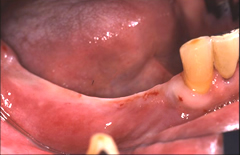

人工歯を支えるためのアバットメント(支台部)をインプラントに接続します。 歯肉が治癒するまで約3週間待ちます。仮歯あり。